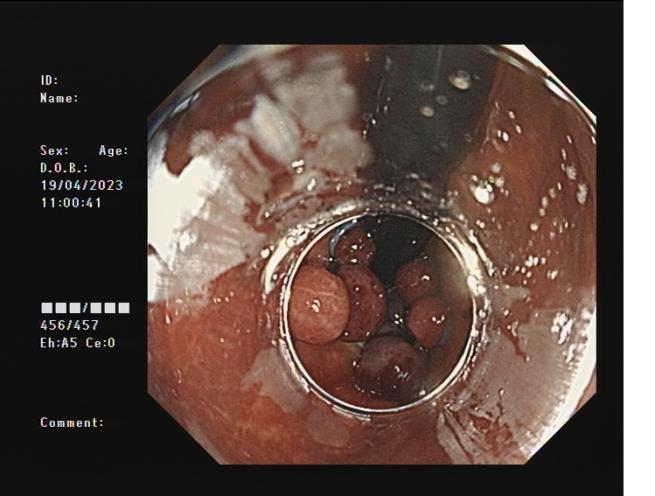

3ec63f6bdf6c49908576319b43de8ed5.Jpeg793b9b4fe5dd4c639a19025be7c58d78.Jpeg

內(nèi)痔                   內(nèi)鏡下套扎術(shù)

內(nèi)鏡下內(nèi)痔套扎術(shù):治療內(nèi)痔并脫出和(或)出血等癥狀,包括II、Ⅲ度內(nèi)痔等。